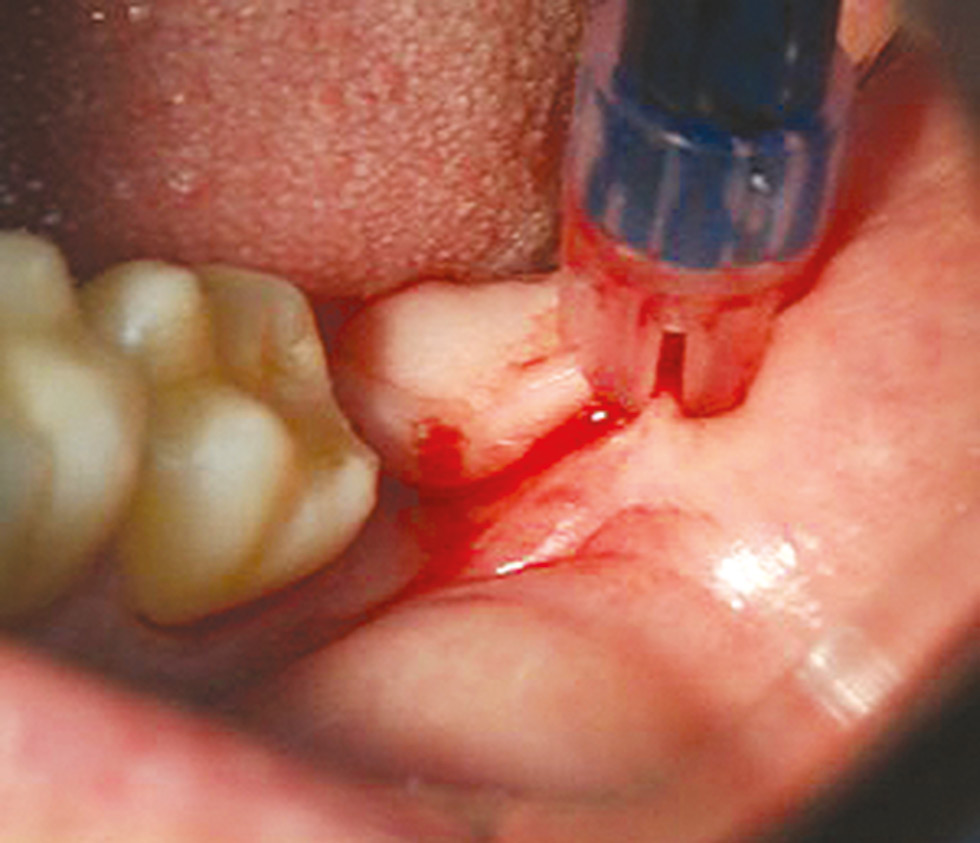

При удалении верхних третьих моляров под проводниковой и инфильтрационной анестезией выполняли разрез в области бугра верхней челюсти, в проекции коронки зуба, посередине альвеолярного отростка вверх и к переходной складке к середине коронки второго моляра. Отслаивали слизисто-надкостничный лоскут. Использовали прямой хирургический наконечник по принципу максимального сохранения костной ткани. При помощи щипцов и прямого элеватора вывихивали зуб. Лунку ушивали (рис. 3).

Рис. 3. Удаление и ушивание лунки зуба 3.8.

Fig. 3. Removal and suturing of the tooth socket 3.8.